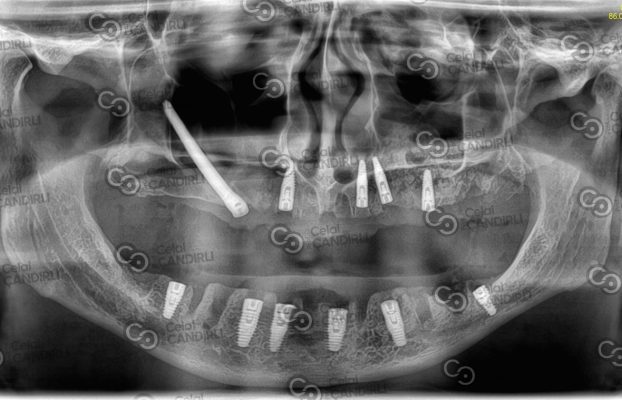

Prof. Dr. With Max Fax Zygoma Center under the expertise of Celal Çandırlı, we have served many institutions and organizations other than our individual patients, here are some of them.